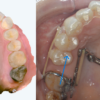

歯周病を専門とする歯科医師と連携し

-

歯ぐきや骨の環境を整える治療(歯周再生療法)を

先に、あるいは途中で行うという選択をすることがあります。

これは、今回の研究が示している

「歯を支える環境の重要性」を、私たちも重視しているからです。